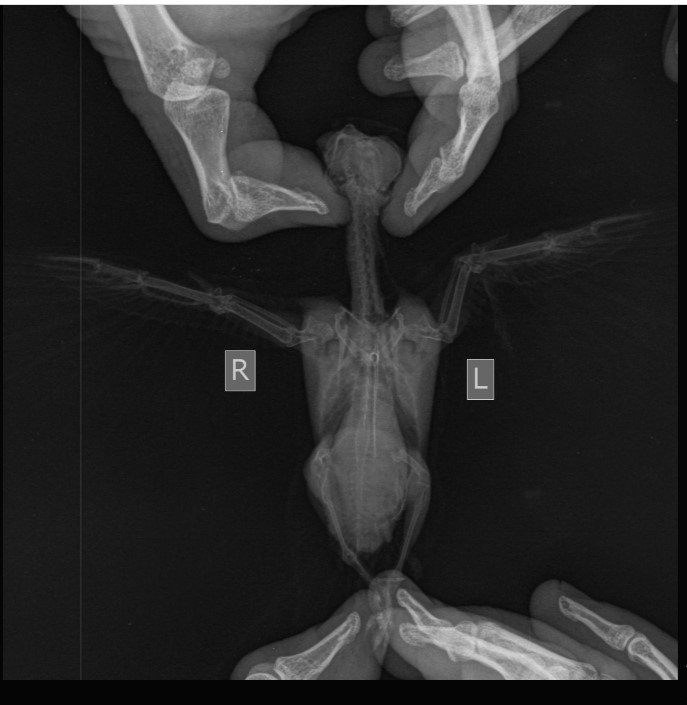

Приветствую  всех.    Я должна это написать .   Это мое предположение, возможно  спорное, я очень долго думала и нализировала, почему  погибла птица.  и я   пришла к выводу , что именно ренгент  крыла мог повлиять на ее смерть . Ничего другого -плохого - ни корм , ни отравление  марганцем, ни то,что держали не в коробке (ерунда это) не могло привести к  параличу птицы , а  ее парализовало ...........  у нее   было  все  отлично - корм насекомые и муравьиные яйца ,  она лазила по клетке, как обезьянка, обихаживала себя , готовилась  к полету -тренировалась .   Все было отлично  до 1  августа.   Ренгент  крыла сделали 25 июля , а 1 августа  ей стало  плохо , она не смогла глотать сверчков , я пришла на сайт сюда , все выше здесь есть, я все сделала,что было предписано , ей  стало немного легче, она смогла глотать выжемку  из насекомых , но не надолго......отнялись лапки и "прилипли"  крылья к телу и переодически  дергалась голова-  это ренгент  повлиял   и ничего другого...........................будьте осторожны, когда несете птицу  на ренгент, узи.  Жужу умерла 7 августа днем . Закопалина даче  и посадили розу.((((((((((((((((((((